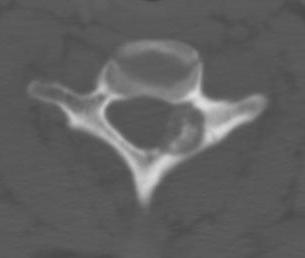

Hounsfield scale

Bone 2000

ST 40

Water 0

Fat -100

Air -1000

Adjust settings to bone or soft tissue